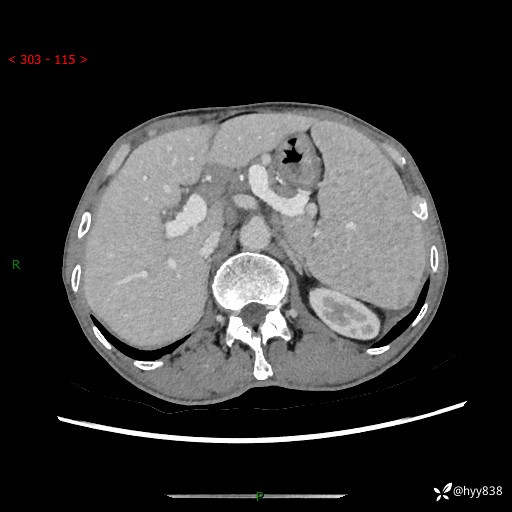

老年男性,脾大并脾脏弥漫粟粒状低密度,淋巴瘤 VS 肉芽肿 VS 血管瘤---结果公布

简要病史: 患者于3月前无明显诱因出现脾大,伴腹部轻微不适,具体不详,无腹痛、腹泻、腹胀,无头晕、头痛、乏力,无恶心、呕吐、呕血,无胸闷、气短、胸痛不适

上腹部CT平扫+增强